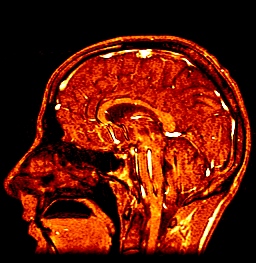

My Brain